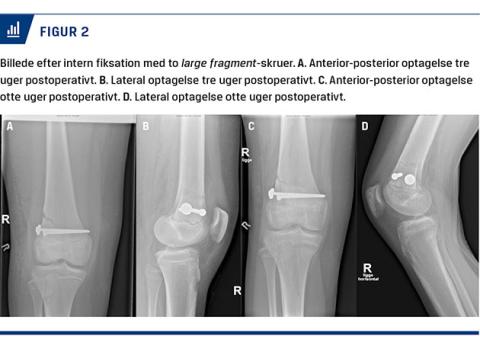

Man forsøgte først lukket reponering i generel anæstesi, hvilket ikke var muligt. Man konverterede til lateral parapatellar adgang, hvor frakturen kunne fritlægges. Efter massiv oprensning for periost i frakturspalten blev frakturen reponeret anatomisk. Stillingen blev kontrolleret palpatorisk og radiologisk på operationsstuen. Efter reponeringen var der ingen mistanke om kar- eller nerveskade. Frakturen blev internt fikseret med to large fragment-AO-skruer (Figur 2). Knæet blev efterfølgende fundet side-, skuffe- og Lachmann-stabilt på operationslejet.

Det postoperative regime omfattede anlæggelse af en ulåst DonJoy-bandage og forbud mod at støtte på benet i seks uger. Patienten startede øjeblikkeligt på ubelastet genoptræning i form af liggende knæfleksionsøvelser. Hun blev set til klinisk og radiologisk kontrol henholdsvis tre og otte uger postoperativt, hvor der ikke var mistanke om skred i fraktur eller osteosyntesemateriale. Ved otteugerskontrollen var hun smertefri og havde ingen subjektive gener. Ligeledes var der nærsolid heling og ingen tegn på vækstkomplikationer (Figur 2).